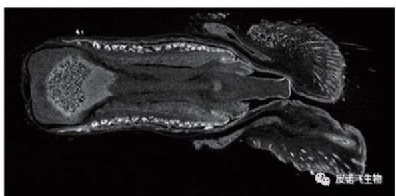

关节组织 生殖器组织

肺部组织 胚胎组织